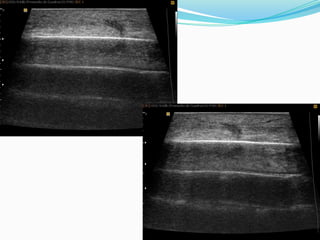

ANISOTROPIA

Es la propiedad que tienen algunos tejidos de variar su ecogenicididad

dependiendo del ángulo de incidencia del haz ultrasónico sobre ellos. La

estructura anisotrópica por excelencia es el tendón.

inserción tibial del tendón rotuliano y vemos que si la sonda no esta perpendicular nos da una falsa

imagen de tendinitis, ya que se ve el tendón hipoecogénico